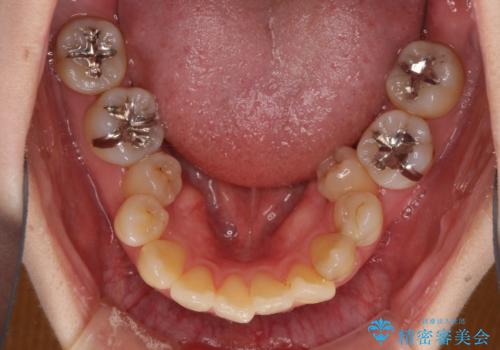

- 下顎の歯が舌側に倒れていることと、前歯の咬み合わせの不具合を気にして来院された患者様です。

受け口傾向の口元であるため、下顎左右小臼歯各1歯を抜歯して歯列を整えることとしました。